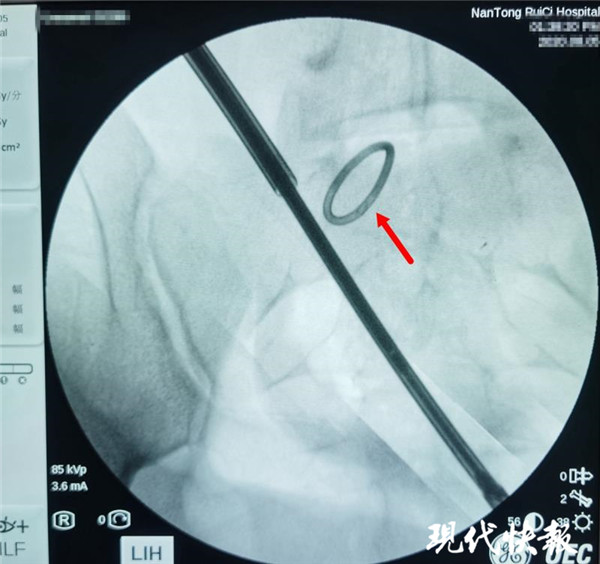

△術(shù)中X光,可清晰看到節(jié)育環(huán)

通過反復(fù)的X光定位,醫(yī)生終于發(fā)現(xiàn)了節(jié)育環(huán)的蹤跡,這枚“O”型節(jié)育環(huán)已經(jīng)跑到了乙狀結(jié)腸中段右側(cè)系膜內(nèi),并且穿透了乙狀結(jié)腸右側(cè)壁肌層,貫穿腸腔。醫(yī)生分離切開腸系膜后,看見有近一半的節(jié)育環(huán)嵌頓在腸腔內(nèi)。之后胡偉和吳忠新相互配合,將節(jié)育環(huán)完整取出,并根據(jù)術(shù)中談話時(shí)患者家屬選擇的手術(shù)方案,對(duì)腸壁的兩處瘺孔進(jìn)行了修補(bǔ)縫合,手術(shù)順利結(jié)束。